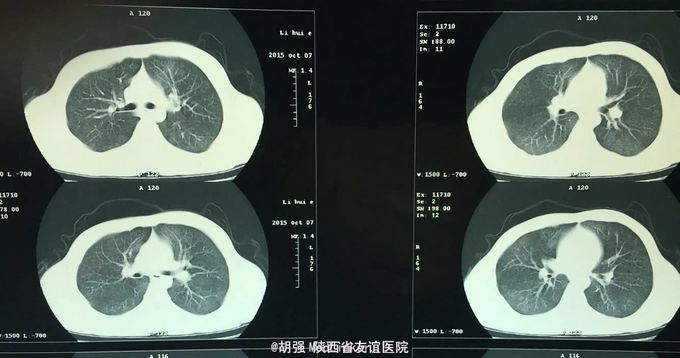

查体:口唇无发绀,咽充血,双侧扁桃体2度大,表面可见脓胎。两肺呼吸音粗糙,可闻及管状呼吸音。余查体无明显异常。 辅助检查:血常规提示白细胞及血小板明显低于正常值,肝功提示转氨酶升高。凝血系列:PT、APTT时间明显延长。T sport试验弱阳性。10月份胸部CT平扫未见明显异常。10月26日及12月12日胸片未见明显异常。12月19日胸部CT提示:两肺斑片状阴影,两侧胸腔积液。